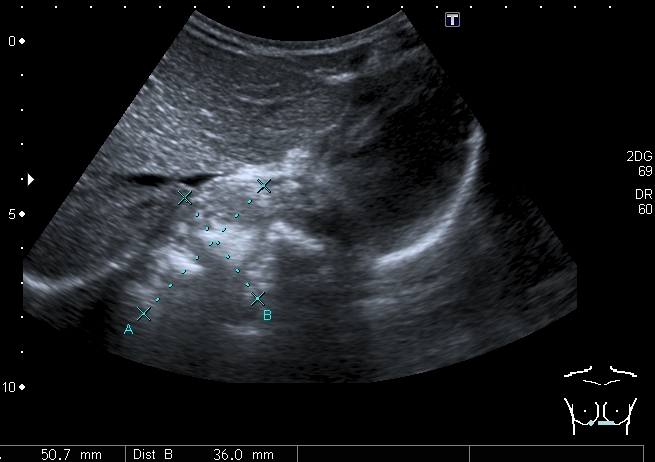

Девочка 4-х лет, жалобы на длительный кашель (оеоло 1-го месяца). В поликлинике выполнена рентгенография органов грудной клетки, выявлены изменения (какие - пока не скажу). Госпитализирована. Направлена на УЗИ сердца. При УЗИ - в самом сердце - патологии не выявлено, но позади него к правому предсердию прилежит полостное образование с акустически неоднородным содержимым.

Анализы крови - не изменены, температуры - нет. Девочка чувствует себя хорошо. Небольшая подсказка: я перешёл с секторального кардиологического датчика на абдоминальный...Serg

Сканы через пищеводное отверстие диафрагмы